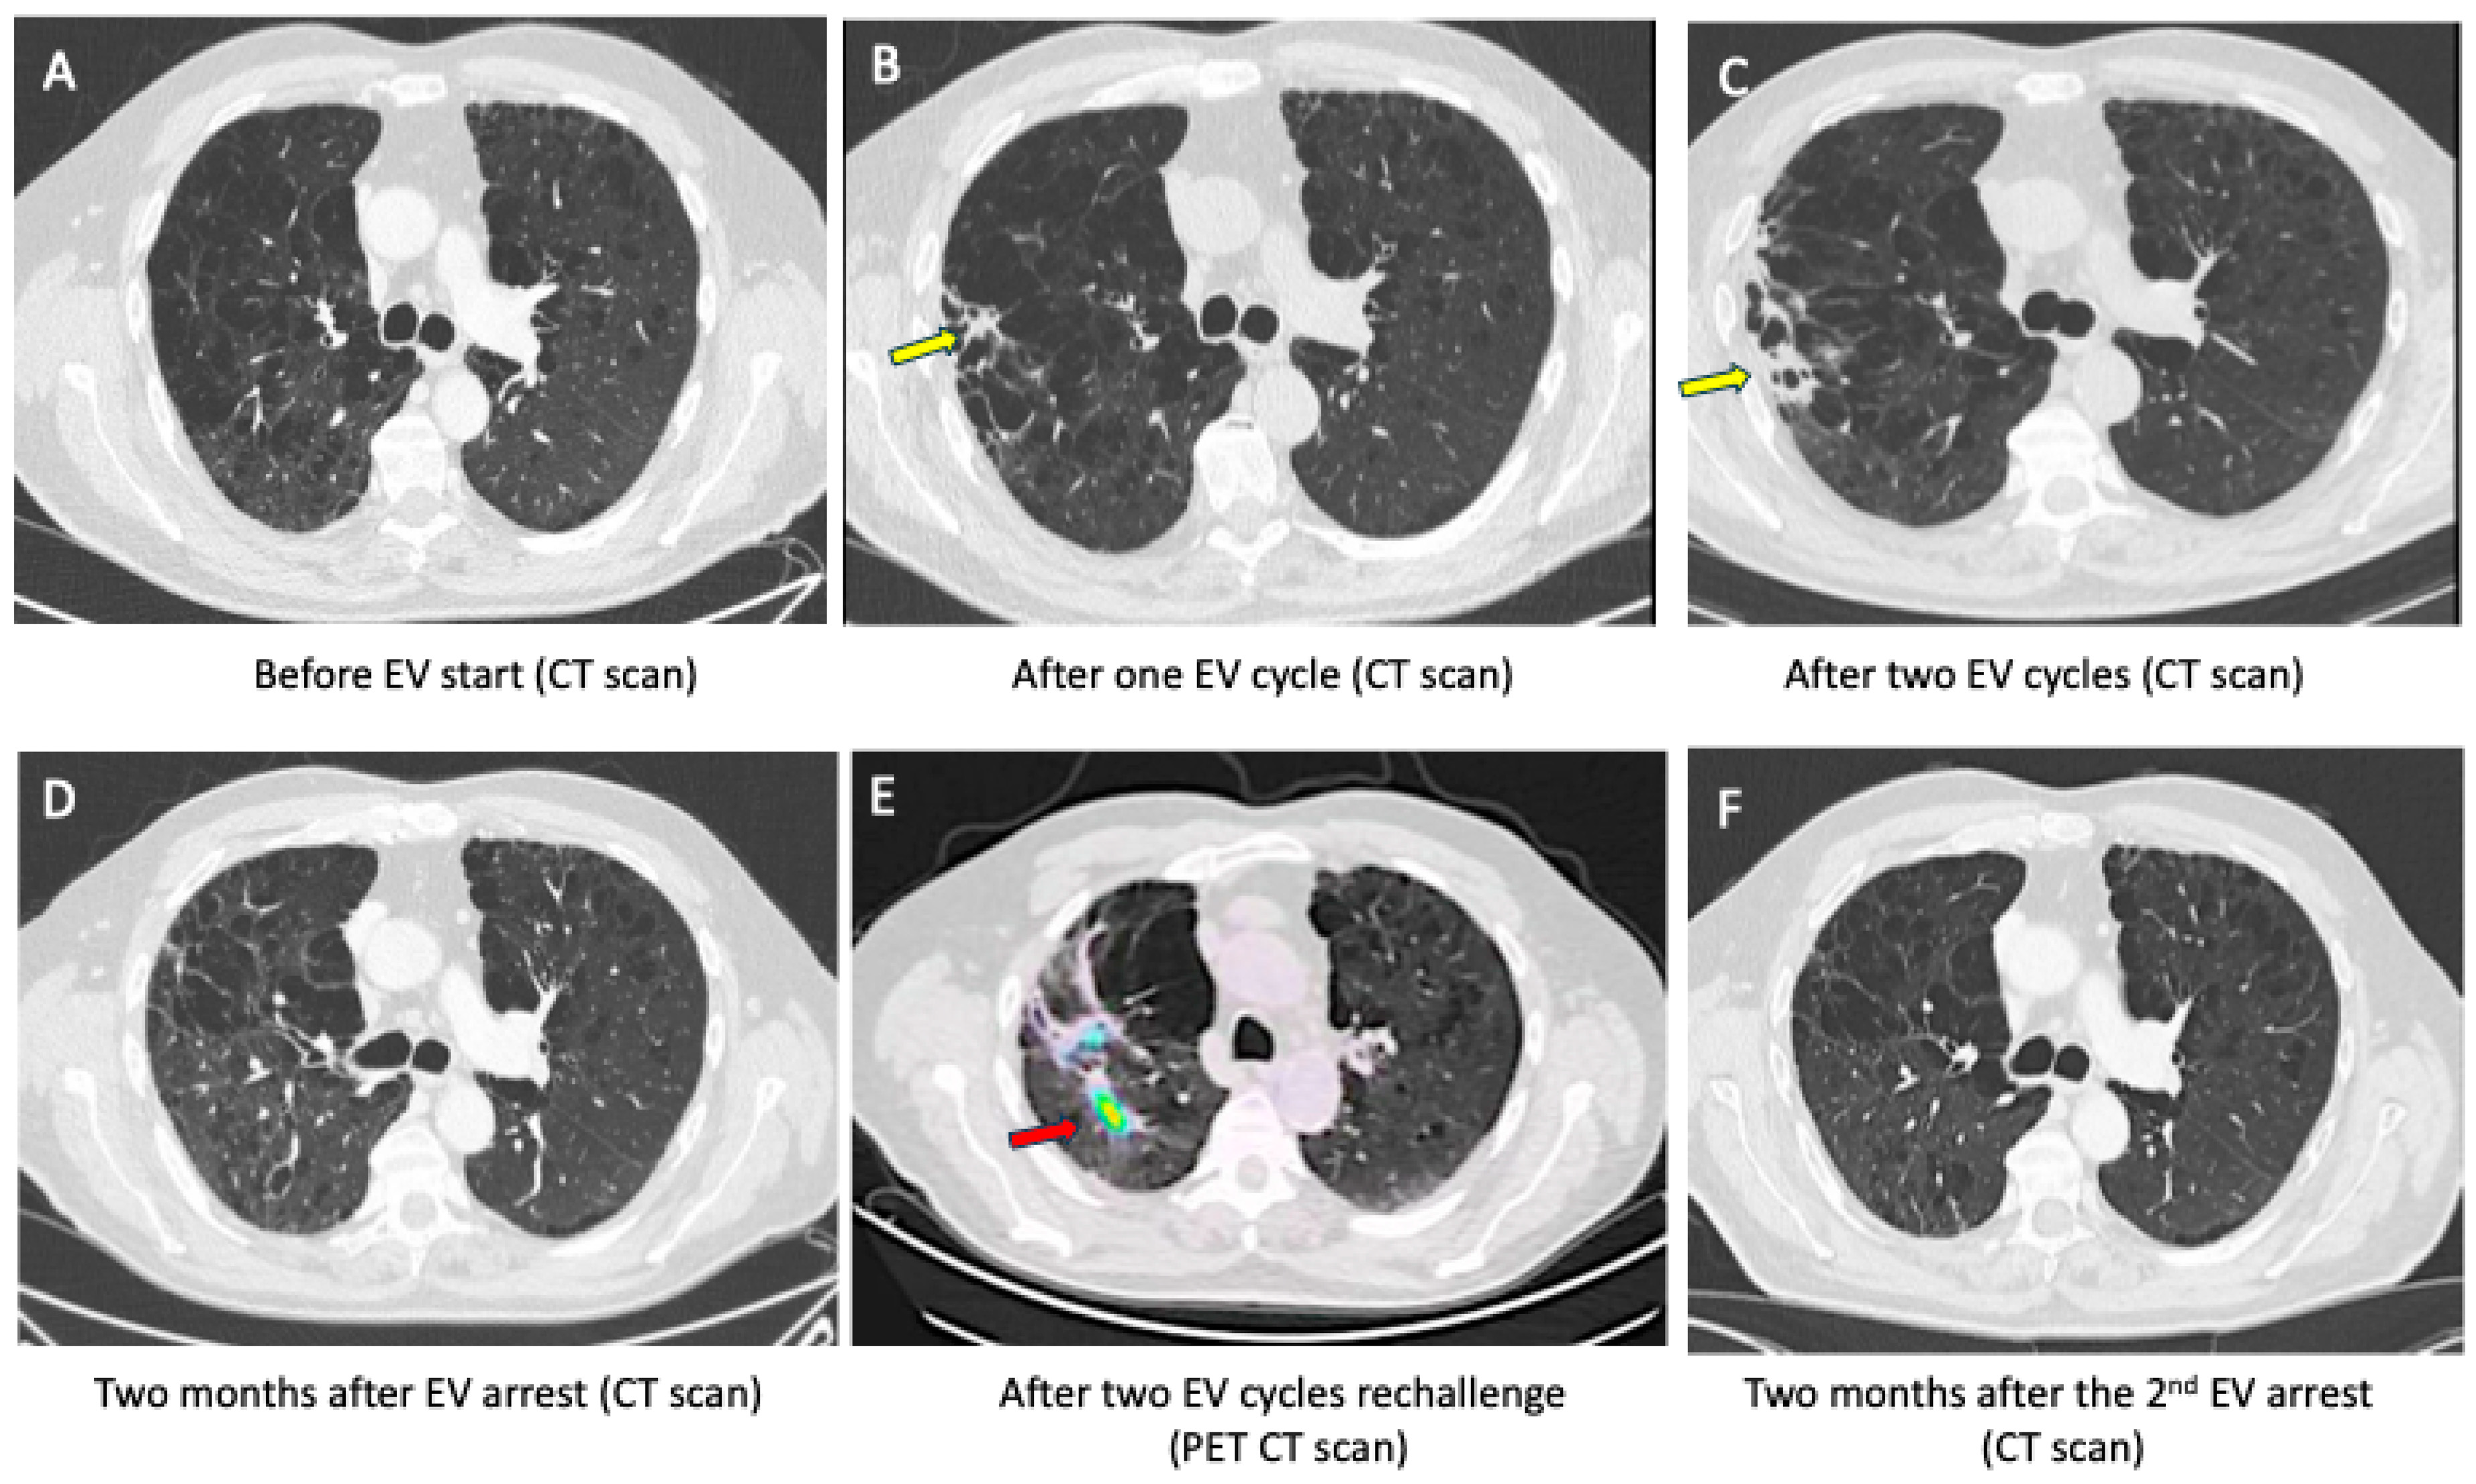

2.1. Case 1 (Priming Patient)